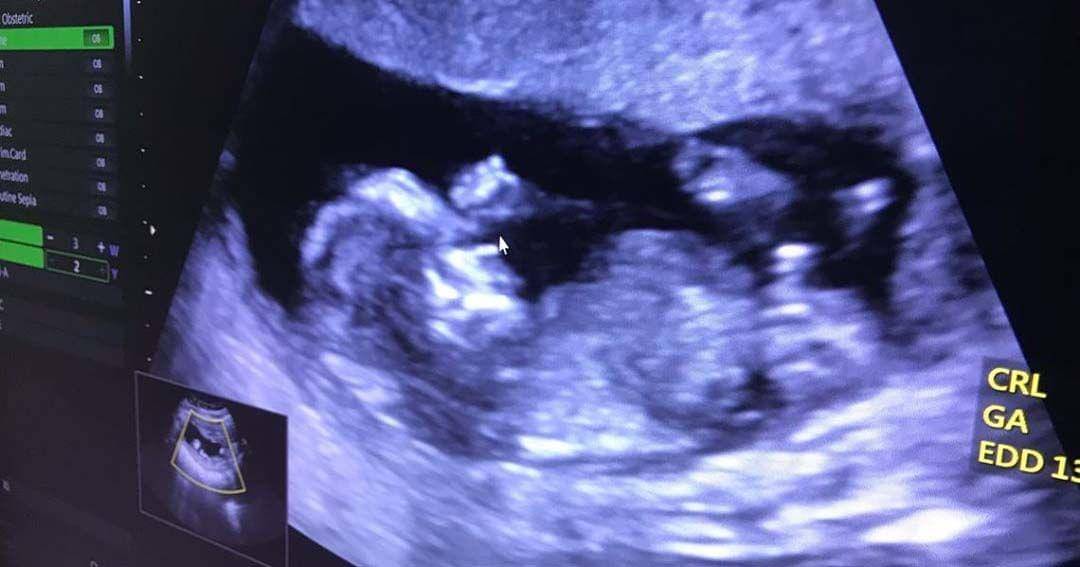

Biby diketahui sempat mengalami pendarahan karena posisi plasenta yang terlalu kebawah yang disebut dengan nama Placenta Previa. Placenta Previa sendiri adalah masalah kehamilan di mana plasenta tumbuh di bagian terendah rahim (uterus) dan menutupi seluruh atau sebagian dari pembukaan mulut rahim.

Sebagian besar kehamilan, plasenta menempel di bagian atas atau samping rahim. Salah satu permasalahan yang menyerang plasenta adalah Placenta Previa. Placenta Previa tumbuh di bagian terendah rahim atau uterus yang menutupi seluruh atau sebagian pembukaan mulut rahim.

Saat memasuki trimester kedua dan ketiga, plasenta harus berada di dekat bagian atas rahim sehingga serviks terbuka untuk memudahkan persalinan. Namun, sebagian plasenta atau seluruhnya dapat menutupi daerah serviks yang disebut dengan Placenta Previa.

Placenta Previa dapat menyebabkan pendarahan hebat selama kehamilan dan persalinan hal ini yang dialami oleh Biby Alraen pada usia kandungan 4 bulan.